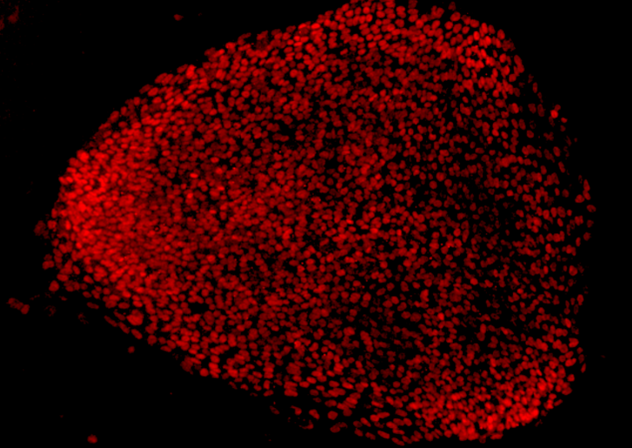

随着CRISPR/Cas9技术在人类干细胞中的应用,研究者就可以在修正特殊的基因突变之后对患者进行健康新型细胞的移植,而视网膜疾病正是干细胞疗法开发的完美模型,因为研究者可以利用先进的手术技术来将细胞注入到其所需的位置。本文研究是一项验证实验,相关结果表明,研究者不仅可以修复一种罕见的基因突变,而且还可以对患者机体的干细胞进行操作,而干细胞的使用就是关键,因为其可以重编程为视网膜细胞。

目前CRISPR技术可以修正13%的干细胞中的RPGR突变,研究者Bassuk指出,该研究结果非常鼓舞人心,因为基因突变一般位于RPGR基因高度重复的序列中,实际上确定基因中的DNA具体序列非常具有挑战性,而研究者并不清楚CRISPR/Cas9技术是否可以正确修正基因的点突变。